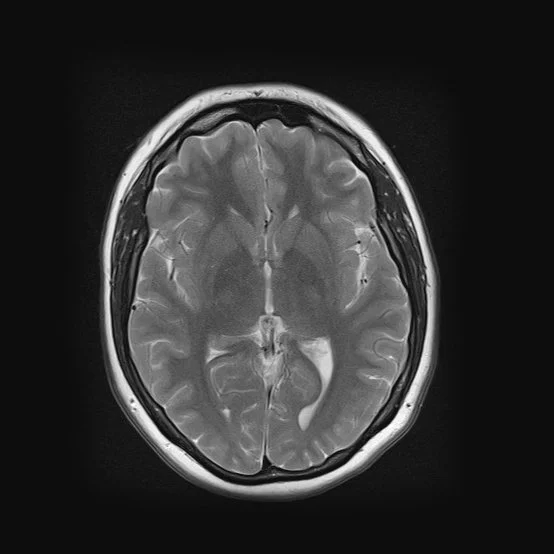

Taking an autoethnographic approach, the artist used her own MRI scans, arranging them to create a visual narrative that mirrors an evolutionary progression. This method not only highlights the physical shifts of the maternal body but also serves as a metaphor for the psychological and emotional changes that redefine the self.

By layering medical imagery into a conceptual framework, the work challenges the notion of identity as static, instead presenting it as fluid, evolving, and deeply intertwined with the lived experience of motherhood.